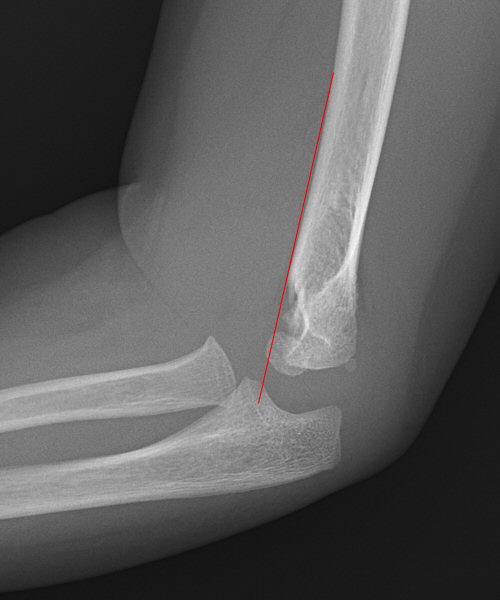

Suprakondylär humerusfraktur, Gartland 1.2, Rogers line delar capitulum radii, behandlades icke-kirurgiskt

- Rogers line/anterior humeral line måste åtminstone tangera capitulum radiis framkant, d.v.s.: [1]